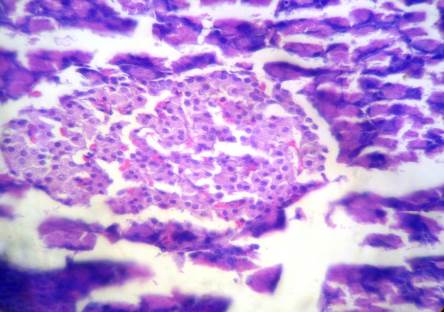

Group I: Normal Control (Saline)

Fig. 8: The normal numbers and volume of the islets cells